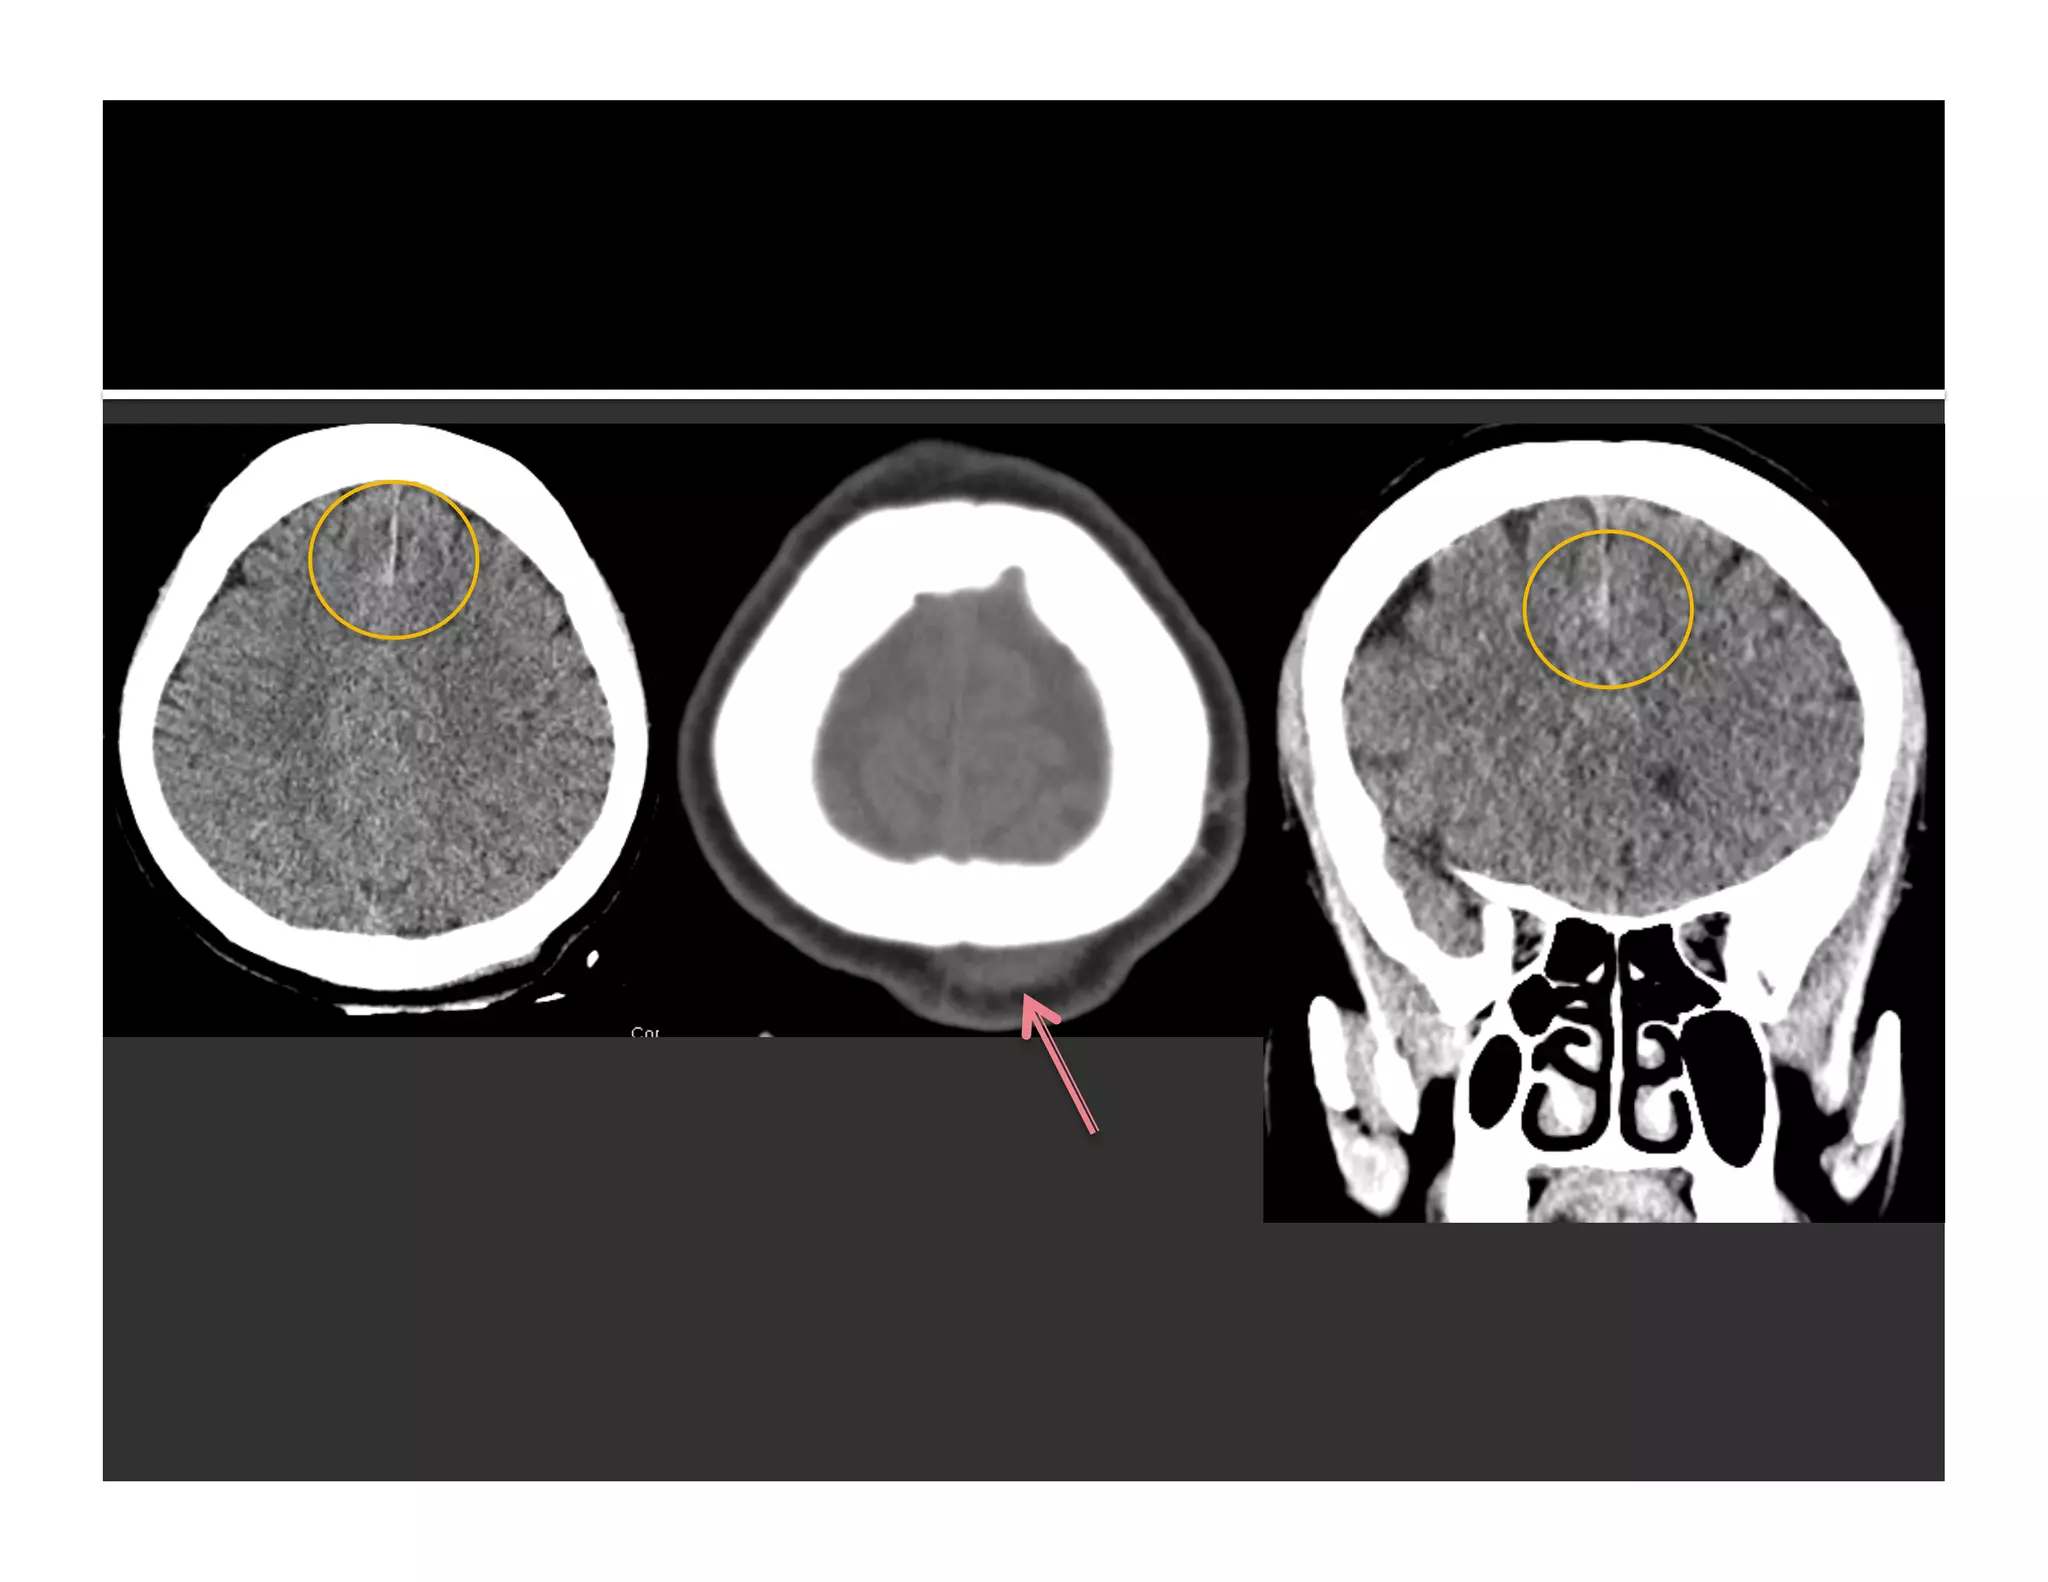

 213 NCCTs

▪ 32 cases with traumatic ICH = 104 foci on either

axial or coronal images

▪ 80 foci were true-positive lesions

▪ 15 true positives not detected on axial images

(15/104 = 14%, in 8 patients)

▪ 14 false-positive findings on axial but excluded on

coronal

 Axial images are less accurate in areas

 Parallel to axial image plane (esp immediately

adjacent to bony surfaces)

 Common areas where false negatives occur

 Floor of anterior cranial fossa

 Floor of middle cranial fossa

 Vertically oriented lesion easier to detect

on coronal reformation than axials

 Horizontal skull fracture

 Enable us to be certain about diagnosis

 Lesion detection

 Floor of anterior and middle cranial fossae

 Tentorial lesions

 Horizontal skull fracture

 Vertically oriented lesions